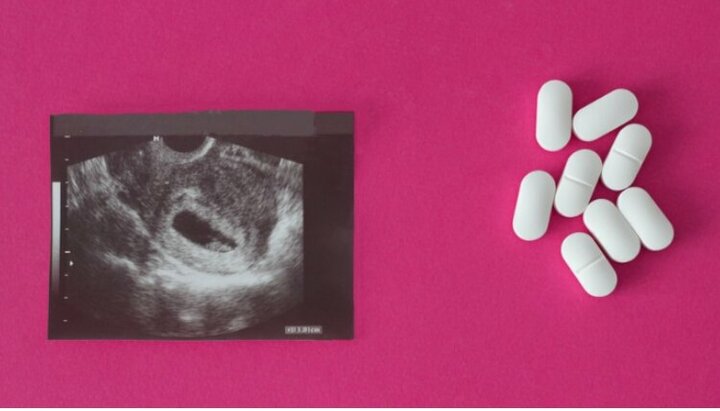

Таблетки для прерывания беременности. Фото: christianheadlines.com

Администрация президента США Джо Байдена намерена разрешить беременным женщинам заказывать таблетки для прерывания беременности по почте во время пандемии, сообщает «ChristianHeadlines».

В Управлении по санитарному надзору за качеством пищевых продуктов и медикаментов (FDA) заявили, что во время посещения клиники увеличивается риск заразиться коронавирусом. Таким образом, препарат можно будет отправлять по почте «при соблюдении всех остальных требований». Его разрешается принимать только на ранних сроках беременности.

Данные, опубликованные в 2018 году FDA, показывают, что химические аборты привели к тысячам случаев побочных эффектов, в том числе к 768 случаям госпитализации и 24 смертям с 2000 года.